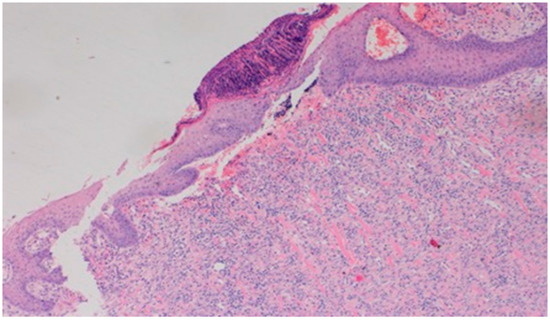

On day 10, all wounds in the control and experimental groups were characterized by a moderate inflammatory infiltration, with a predominance of granulocytes, reaching the dermis. In the experimental group D1, inflammation was at the same level as on the 5th control day. The experimental group D2 and the control group K, treated successively with the 1% nanosilver ointment and sulfathiazole, showed a greater intensity of inflammation in relation to the 5th control day. In group D3, treated with a mixture of 1% propolis and 1% nanosilver, a regression of the inflammatory infiltration, from large to medium, and depth, from adipose tissue to the dermis, was observed. In the experimental group D1, treated with the 1% propolis ointment and control K, treated with sulfathiazole, on day 10, a slight epidermization appeared. On day 10, additionally, all the wounds from the experimental and control groups showed slight superficial necrosis and were characterized by a moderate neovascularization. The histopathological findings from day 10 are presented in Table 9 and Figure 15, Figure 16 and Figure 17.

Figure 17. Focal epidermization under superficial necrosis (100×, H-E) in the wound treated with the 1% propolis ointment on day 10.